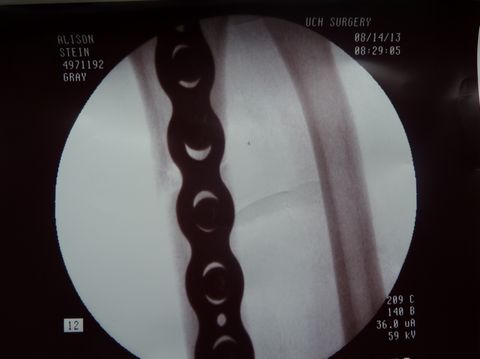

He fitted the margins perfectly back into place, laid a

plate into position, drilled a few holes, and screwed the plate

onto the bone.![]() |

![]() |

Dr. Gray used flouroscopy to confirm that the fracture margins were in perfect alignment, secured by three screws proximal and three screws distal to the fracture. |

|

| In fact, one view (below right) shows such tight apposition and such perfect alignment, that one cannot even see the fracture margins. | |

Dr. Gray checked all of her wrist bones (left), applied a new plaster splint and a new sling, and Alison's I.V. line was removed about 2.5 hours after it was inserted. What a great surgeon and professional team! |